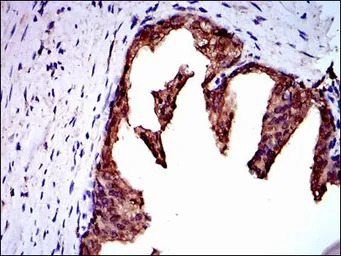

IHC-P analysis of prostate cancer tissue using GTX60546 NEDD8 antibody [5B8].